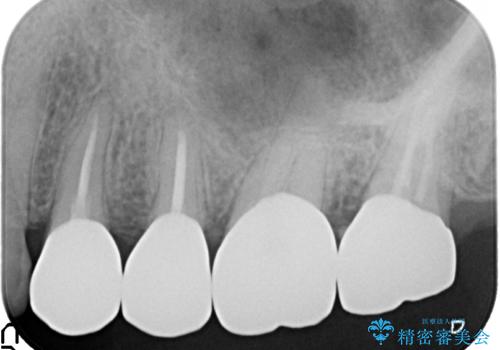

放置してしまった深い虫歯の治療

虫歯の深化により根管治療、歯周外科手術を行い歯肉の状態を改善し精密なセラミッククラウンを製作する治療を計画します。

- 50万円(仮歯・ファイバーコア・ジルコニアクラウン×4 歯周外科)費用は治療当時の料金となります

セラミック治療の長期的な予後を見込むために、根管治療、歯周外科を行いクラウン装着前の環境を整えておくことが肝要です。